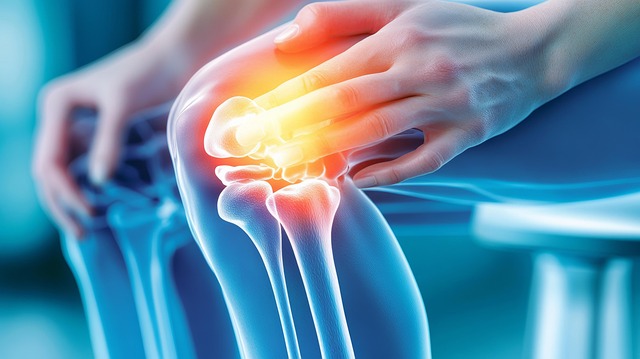

2-3. 염증 및 부종 완화

콘드로이친은 염증 매개 물질의 분비를 줄이고, 관절 내 점액막(시노비움)의 염증(시노비티스)을 억제하는 데 효과적입니다. 덕분에 부종 완화 및 붓기 감소에 도움이 됩니다.

2-4. 관절 기능·운동 능력 개선

통증과 강직 감소로 보행, 계단 오르내리기, 일반 활동 수행이 용이해집니다. 일부 연구에서는 셀레콕시브와 유사한 수준의 기능 개선 효과가 나타났습니다.